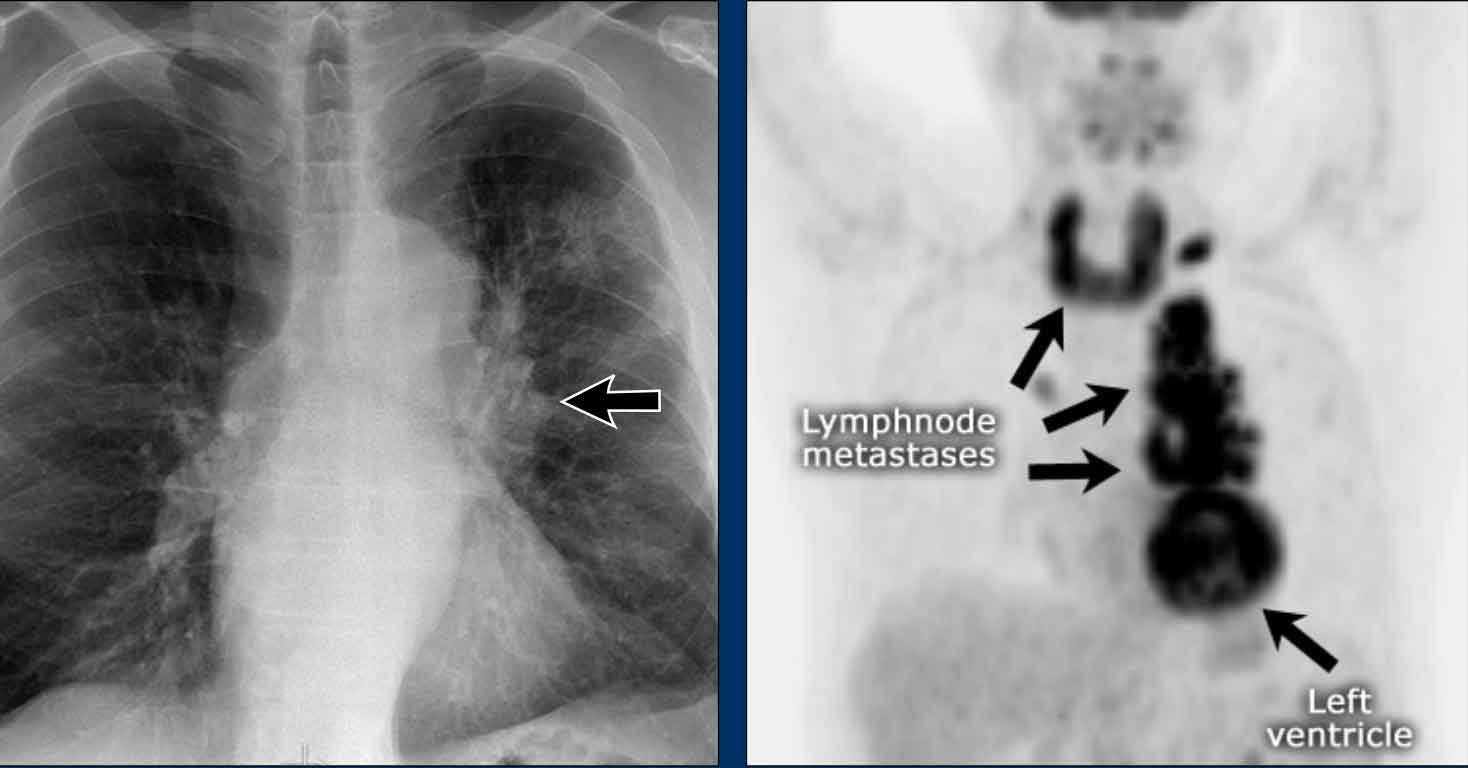

Displacement of the Azygoesophageal Line (2) – Subcarinal Lymphadenopathy

A common cause of displacement of the azygoesophageal line is subcarinal lymphadenopathy (station 7).

On the chest X-ray, note superior displacement of the azygoesophageal line just below the carina, consistent with enlarged subcarinal lymph nodes (black arrow).

Additional right paratracheal lymphadenopathy is seen, displacing the right paratracheal stripe (white arrow) and deviating the trachea to the left.

Continue with PET-CT...

PET Imaging

• PET-CT demonstrates extensive hypermetabolic lymphadenopathy in the mediastinum and neck, which is more conspicuous than on chest radiography.

• Cervical lymph nodes are involved—an important finding as they are accessible for biopsy.

Continue with images of CT and ultrasound...

CT Imaging

• Contrast-enhanced CT shows bulky subcarinal lymphadenopathy displacing the azygoesophageal recess and compressing the left atrium.

• Biopsy of a cervical node confirmed small cell lung carcinoma.